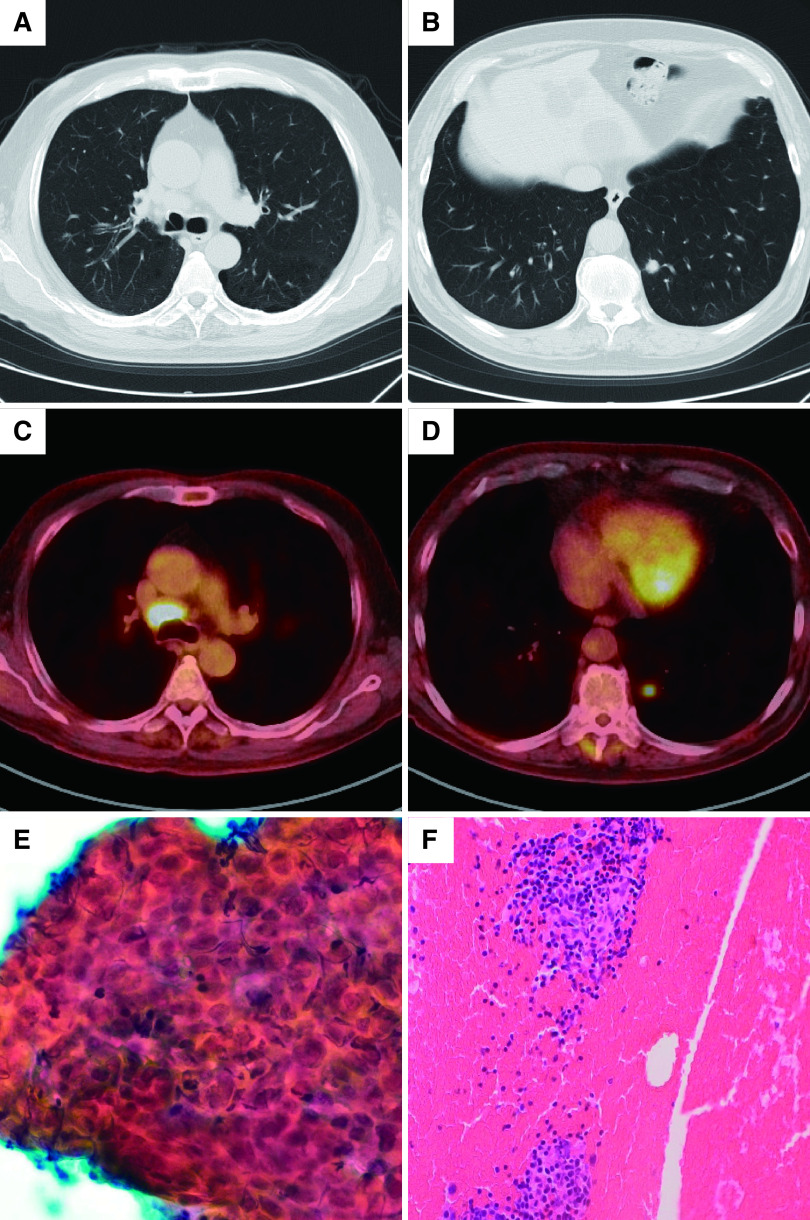

A 71-year-old man was diagnosed as having right primary lung squamous cell carcinoma, clinical stage IIIA, but he refused treatment. However, the right upper lobe nodule and lymph node (LN) #4R showed gradual shrinking without treatment. Four years after the diagnosis, a new nodule was detected in the left lung field. We considered that this new nodule might be metachronous primary lung cancer, and hence resected it for diagnosis and treatment. The tumor in the left lung was diagnosed as basaloid squamous cell carcinoma, and that in LN #4R was diagnosed as squamous cell carcinoma with keratinization. Therefore, the patient was diagnosed as having metachronous primary lung cancer that developed during the spontaneous regression of locally advanced lung cancer.